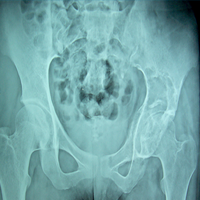

Case:4 GCT Acetabulum

Pre-Op

Post-Op Scraooing + B.G